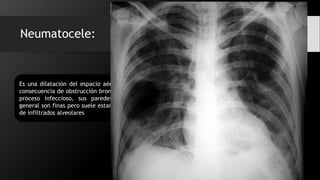

Neumatocele:

Es una dilatación del espacio aéreo como

consecuencia de obstrucción bronquial por

proceso infeccioso, sus paredes por lo

general son finas pero suele estar rodeado

de infiltrados alveolares

Neumatocele: Es una dilatacióndel espacio aéreo como consecuencia de obstrucción bronquial por proceso infeccioso, sus paredes por lo general son finas pero suele estar rodeado de infiltrados alveolares